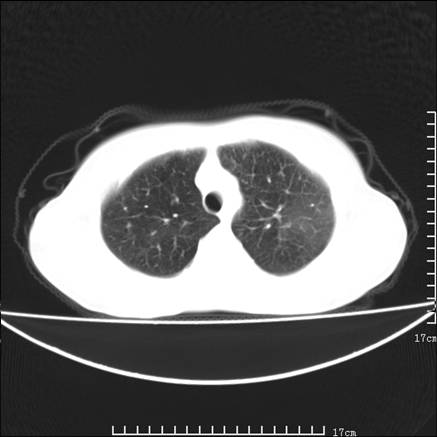

女,46岁,患胃溃疡多年,溃疡大小约1.0cm左右,后于5年前手术,病理为胃癌。主诉:半月前感冒后胸闷,气短,有咳嗽,无明显咳痰,无发热。偶有腰背部不适。

以下为高分辨扫描图像

双肺小叶间增厚,双肺散布粟米影和磨玻璃状影,以双肺上叶为重。结合病史考虑转移(癌性淋巴细管炎)可能性大。

结合病史:认为是典型肺部癌性淋巴管炎、淋巴结转移。请看图解。

正如caihe主任所言,影像表现结合临床病史应该支持肺癌性淋巴管炎;上肺大片边缘不清的渗出病变,多系感染所致,临床有感冒病史并咳嗽表现。肺癌性淋巴管炎临床一般无咳嗽、咳痰症状。

肺癌性淋巴管炎征象分为主要征象及合并征象,主要征象包括:

1、近肺门支气管血管周围间质结节状增厚;

2、小叶间隔结节状增厚;

3、小叶中央间质结节状增厚;

4、胸膜下间质结节状增厚。

合并征象为:纵隔淋巴结增大,胸腔积液,肺多发随机分布的小结节等。